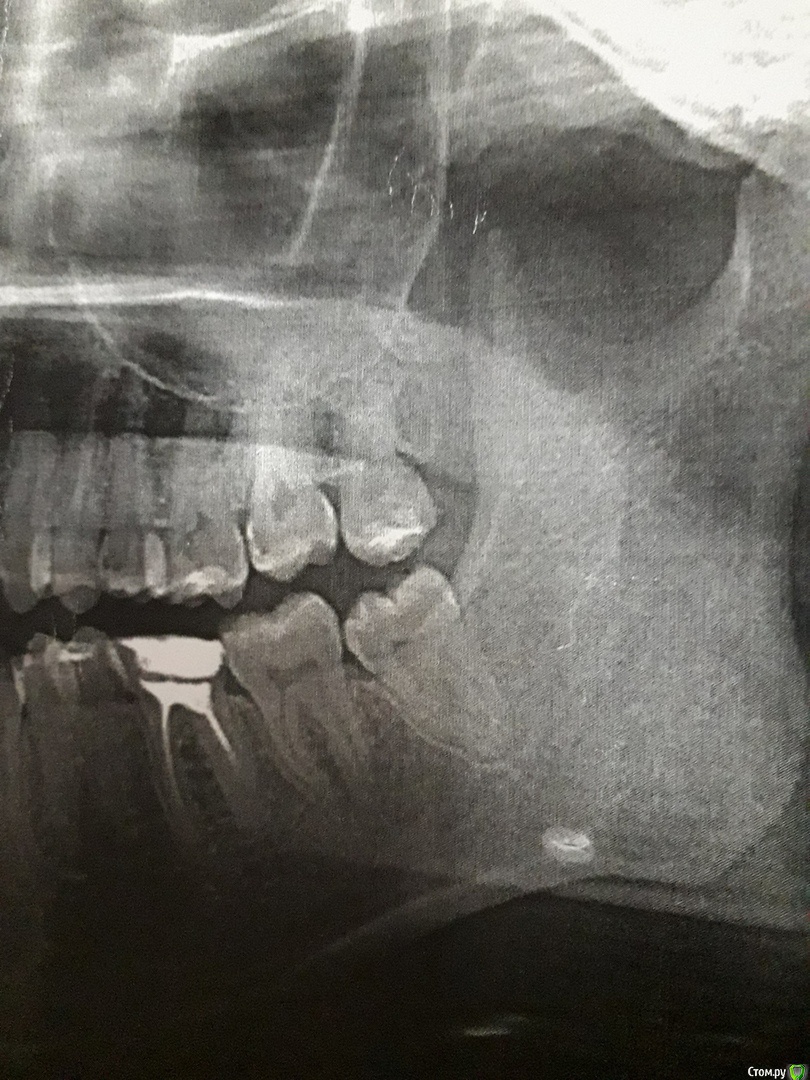

Sveta_000 Опубликовано 28 декабря, 2018 Поделиться Опубликовано 28 декабря, 2018 Добрый день.Болит зуб мудрости(верхний), планируется удаление 4 января. Но из-за болей переживаю, поскольку непонятно, что с каналами.И вообще можно ли ждать до 4 или надо уже бежать. А скоро в поликлинике будут выходные(Помогите, пожалуйста, понять насколько все плохо.Сейчас на зубе временная пломба, она третий день и боли после ее появления усилились. Спасибо Ссылка на комментарий